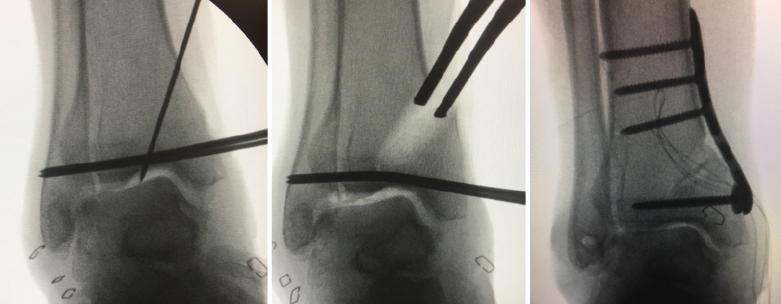

Figura 3. Pasos de la plafonplastia con reconstrucción del ligamento lateral externo en artrosis en varo (caso del Dr. Sergio Tejero).

La meta de la SMOT es la reconstitución o modificación del eje del tobillo para modificar la carga articular y, de esta manera, disminuir o retrasar la progresión de la lesión al cartílago articular(15,16,17,18). Dependiendo de los grados necesarios para la corrección, la osteotomía puede ser conformada por una cuña de apertura medial (Figuras 1 y 2) o, si se requieren > 10° de corrección o una sindesmosis fusionada, una cuña de cierre lateral para evitar una discrepancia de longitud importante(19). Cualquiera que sea la técnica, suele incluirse osteotomía del peroné en ambos casos. Si el peroné tiene claramente una longitud mayor a la fisiológica, restaurar la posición neutra del astrágalo resulta imposible. Knupp et al.(20) realizaron una modificación a la clasificación de la artrosis en varo de tobillo mediante la adición de un algoritmo de tratamiento para los procedimientos extraarticulares. Esta nueva clasificación permite categorizar los distintos tipos de artrosis de tobillo en varo y facilita la decisión terapéutica, especialmente cuando una SMOT aislada resulta insuficiente. Por otra parte, se puede añadir a este procedimiento una osteotomía intraarticular (plastia de pilón tibial o plafonplastia) si se observa persistencia de la inclinación astragalina por artrosis unicompartimental (Figura 3).